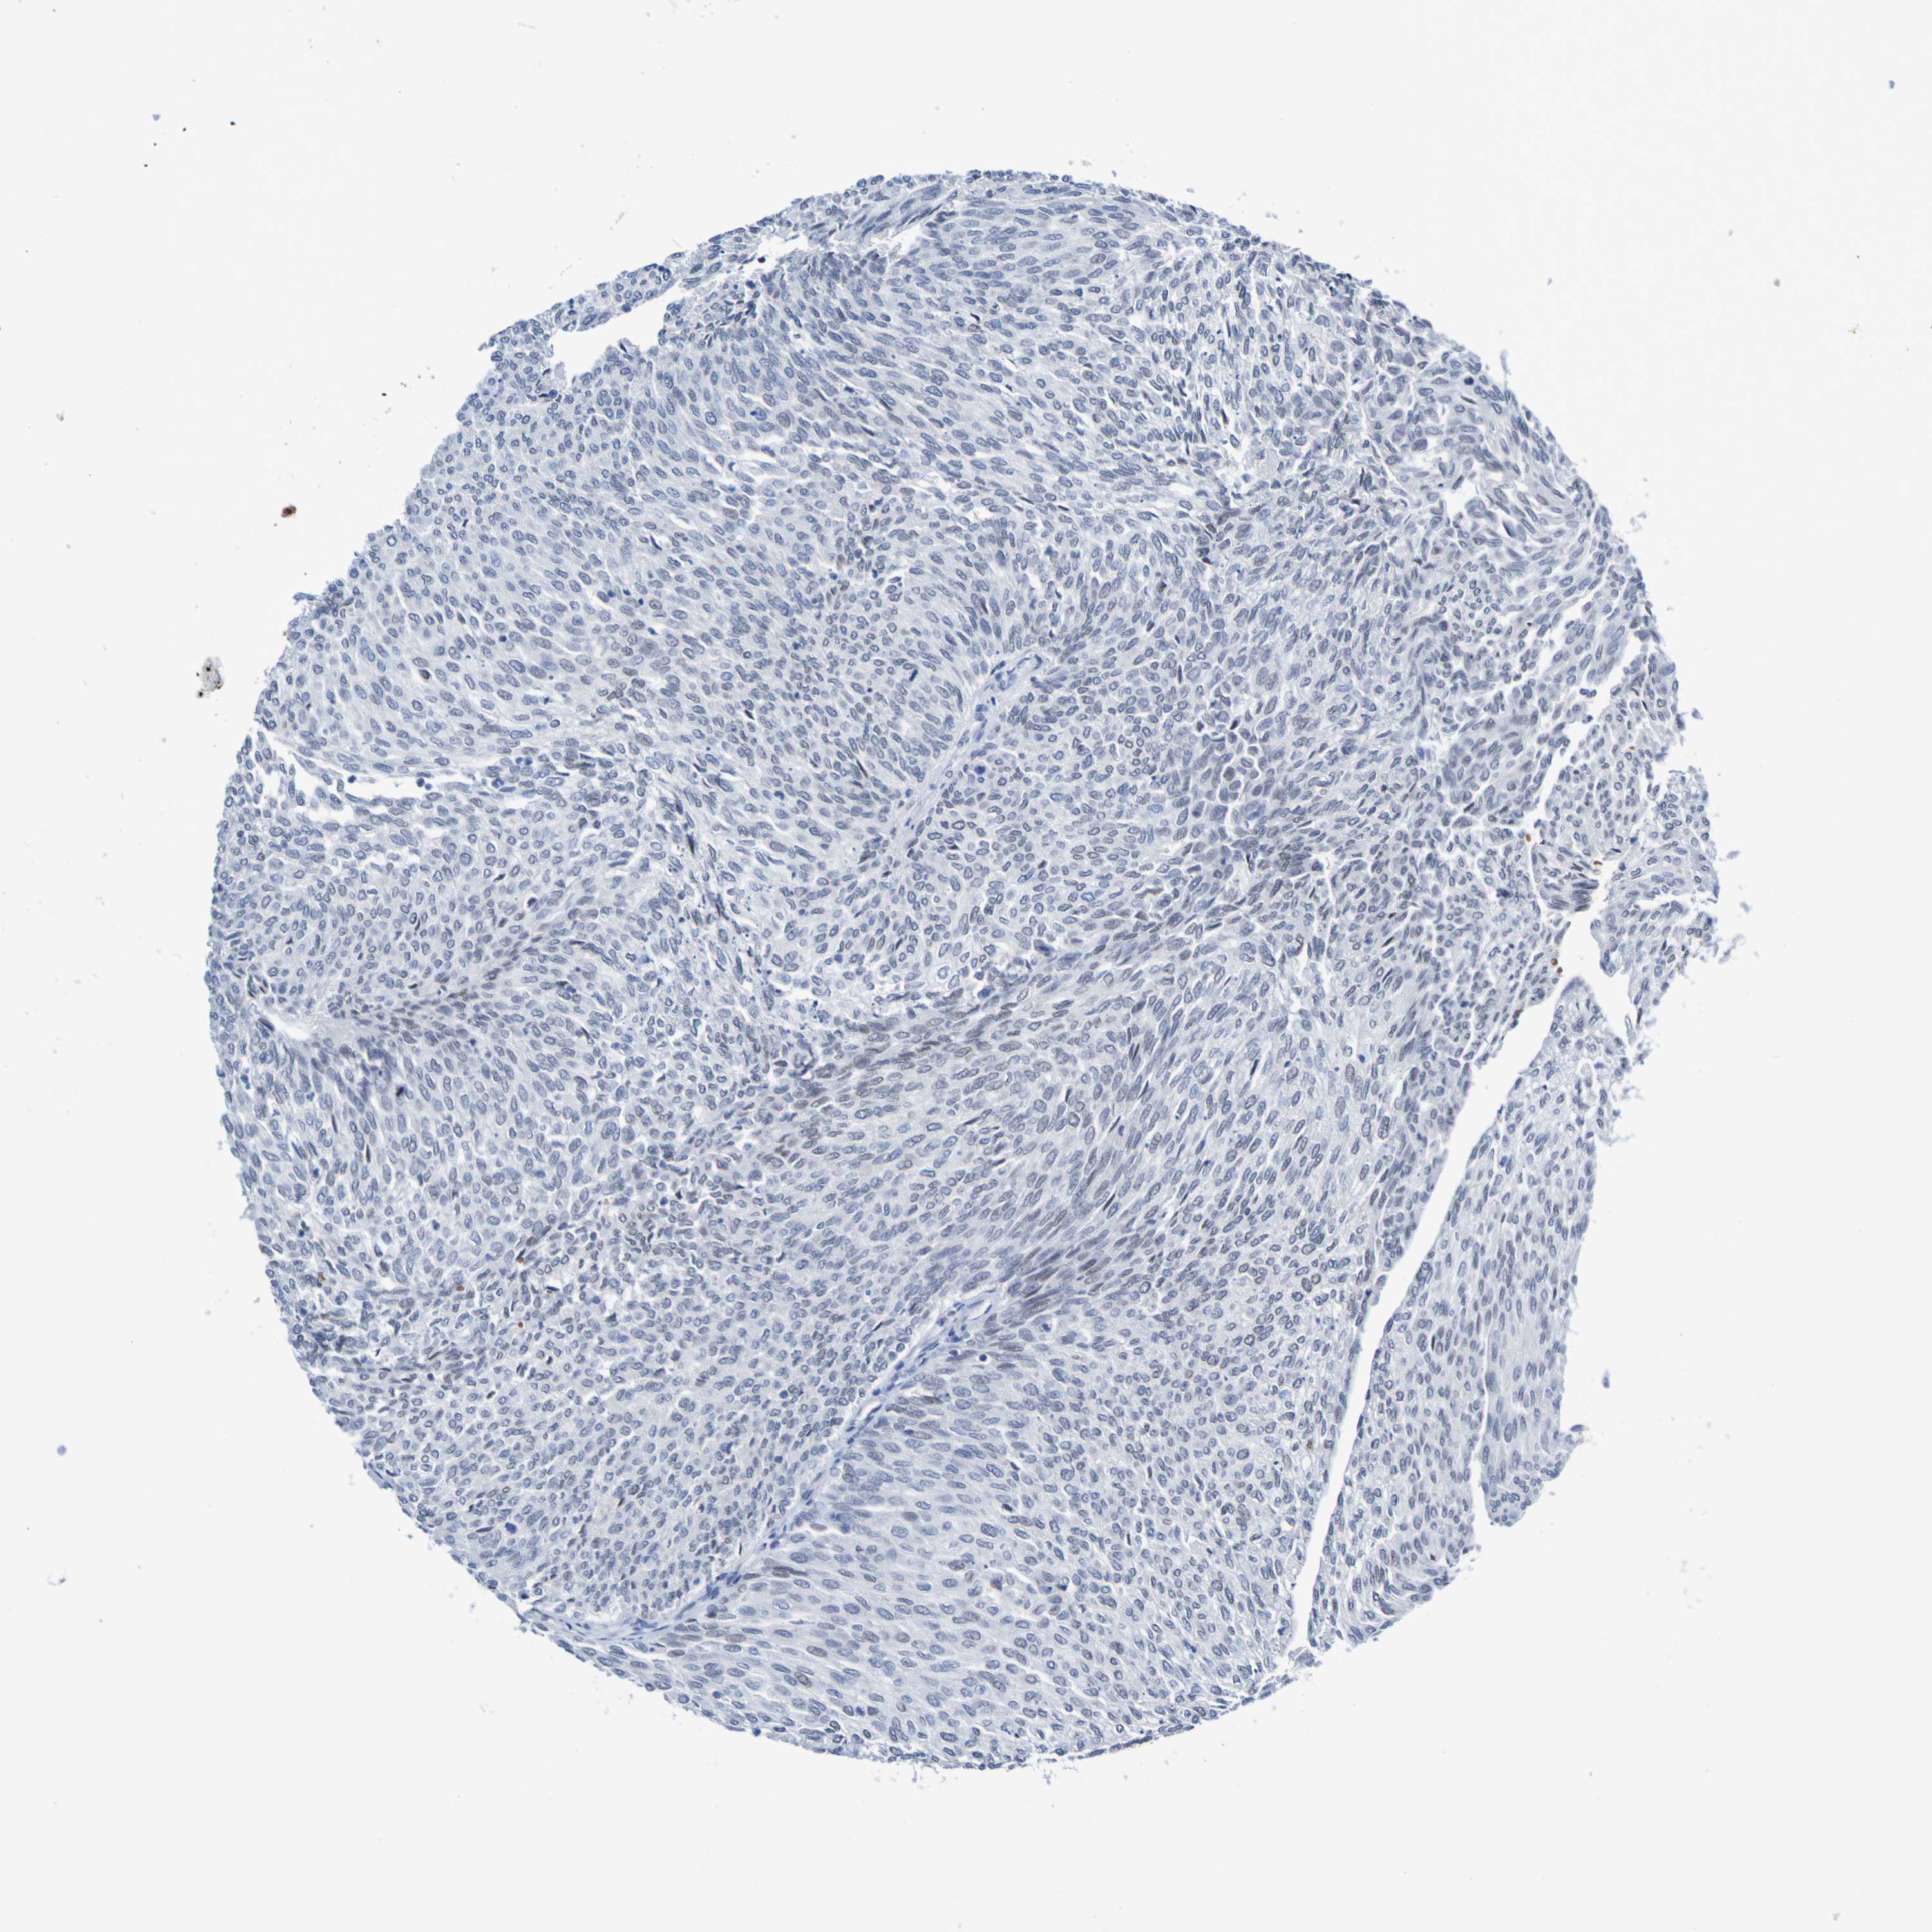

UROTHELIAL CANCER - Protein expressioni

A mouse-over function shows sample information and annotation data. Click on an image to view it in a full screen mode. Samples can be filtered based on level of antibody staining by selecting one or several of the following categories: high, medium, low and not detected. The assay and annotation is described here.

Note that samples used for immunohistochemistry by the Human Protein Atlas do not correspond to samples in the TCGA dataset.

Antibody stainingi

Antibody staining in the annotated cell types in the current human tissue is reported as not detected, low, medium, or high, based on conventional immunohistochemistry profiling in selected tissues. This score is based on the combination of the staining intensity and fraction of stained cells.

Each image is clickable and will lead to virtual microscopy that enables deeper exploration of all samples and also displays staining intensity scores, fraction scores and subcellular localization as well as patient and tissue information for each sample.

Antibody HPA011356

Staining

High

Medium

Low

Not detected

Intensity

Strong

Moderate

Weak

Negative

Quantity

>75%

75%-25%

<25%

None

Location

Nuclear

Cytoplasmic/membranous

Cytoplasmic/membranous,nuclear

Urothelial carcinoma, Low grade

Urothelial carcinoma, High grade